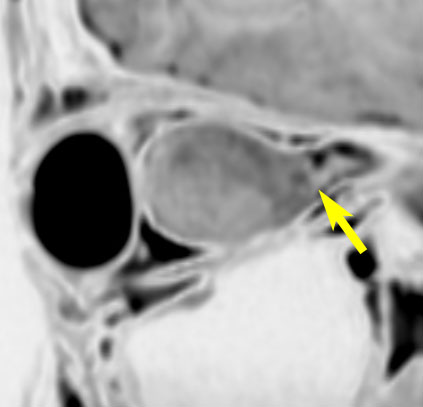

眼窩内に限局する視神経膠腫:神経鞘腫と鑑別が難しいもの

主訴は進行性の眼球突出です。視力低下は軽度で,視野欠損は左眼の下半分でした。入院前の画像では眼窩内神経鞘腫を疑う画像でした。

しかし,CISSの画像では中枢側の視神経との連続性があり,これではじめて視神経膠腫と診断できました。もちろん毛様細胞性星細胞腫です。眼球,眼球運動,眼瞼の動きを温存して腫瘍を眼球後極から切断して全摘出しました。